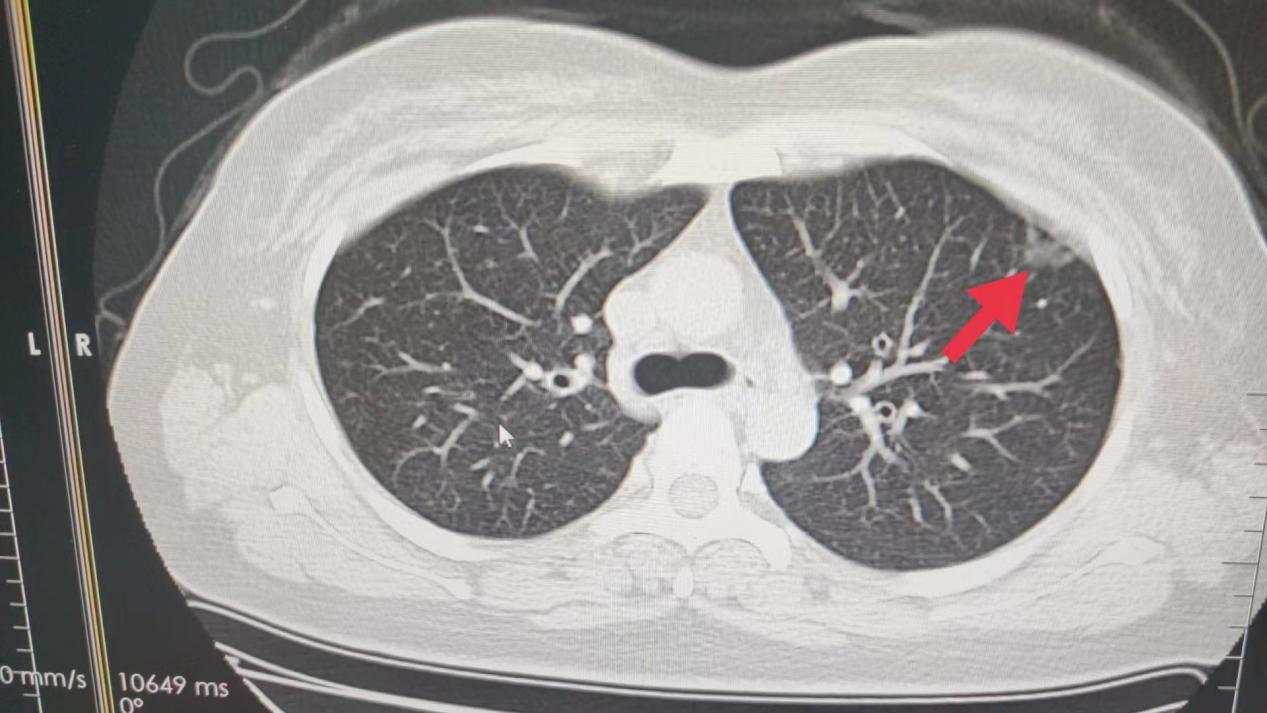

09、**女士,44岁

于2023年10月16日在银川仁泰体检部体检,低剂量肺部螺旋CT提示:左肺上叶前段(im17)见约15*5mm结节,见毛刺征、分叶征、胸膜凹陷征。建议客户到三甲医院进一步诊治。2023年10月31日跟踪回访,客户家属告知,已在当地某三甲医院完成肺部手术,目前恢复中。